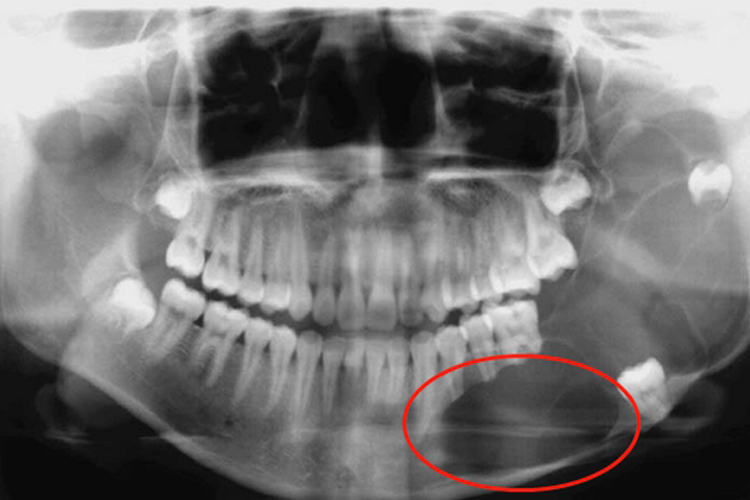

成釉细胞瘤生长缓慢,病程较长,最长可达数十年。好发于下颌骨磨牙区和升支部,早期可无症状,但随病变发展可使颌骨逐渐膨大,膨隆多向唇颊侧发展,造成畸形,左右面部不对称。长大的肿瘤可使骨密质受压变薄,触之有乒乓球感。

如肿瘤侵犯牙槽突,可使牙松动位或脱落。肿物发展穿破骨密质侵入口腔黏膜下时,其被覆的黏膜表面可见溃烂、疼痛。随着肿瘤的增大,可能会影响下颌骨的活动度,甚至可能发生吞咽、咀嚼和呼吸功能障碍。当肿瘤压迫下牙槽神经时,患侧下唇及颊部可能感觉麻木不适。如肿瘤发展很大,骨质破坏较多,可发生颌骨病理性骨折。